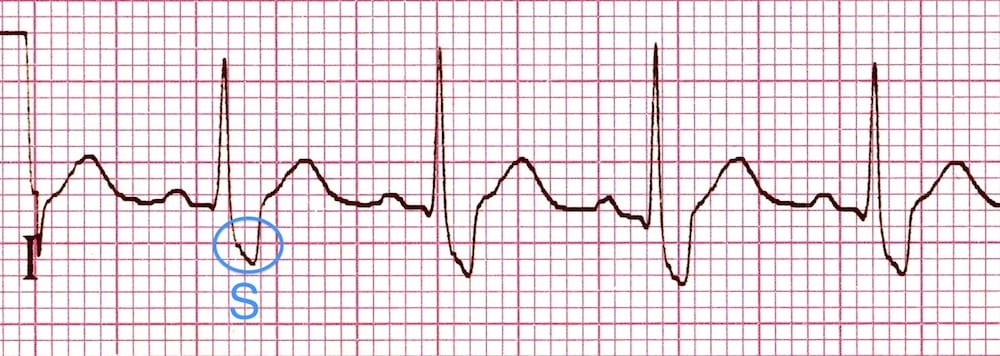

V6: Widened, slurred S wave in V6

QRS Morphology in Lateral Leads

- Wide, slurred S wave in lateral leads (I, aVL, V5-6)

- There is delayed activation of the right ventricle as depolarisation originates from the left ventricle across the septum. This produces a secondary R wave (R’) in the precordial leads, and a wide, slurred S wave in lateral leads